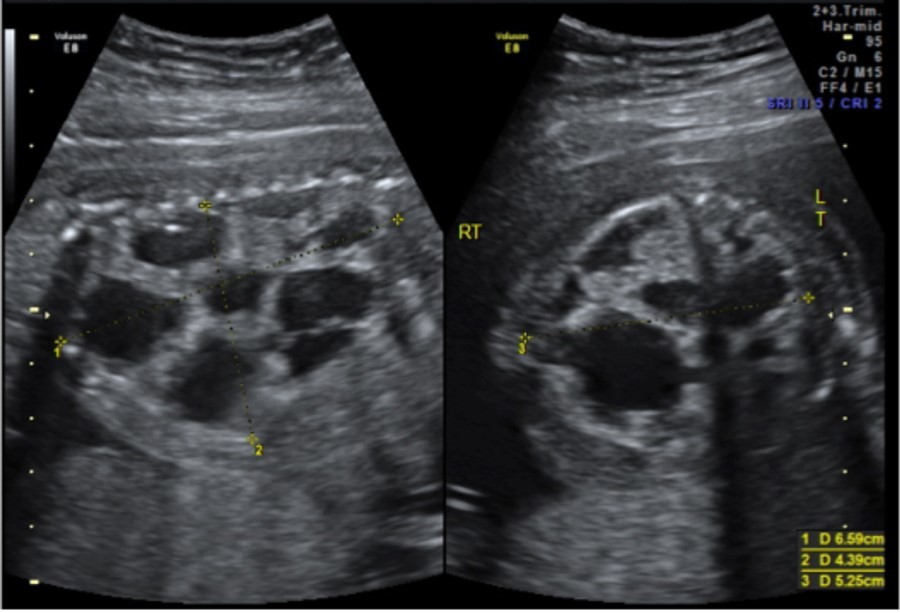

The infant, born weighing 3,015 grams, was intubated at 1 minute of life due to noted bradycardia and no respiratory effort. With positive pressure ventilation on 100% oxygen, the infant had oxygen saturations of 80% and a heart rate of 150. Apgar scores were 6 and 7 at 1 and 5 minutes respectively. The neonate ultimately required vasopressor support and a left sided tension pneumothorax was noted requiring chest tube placement. Thoracotomy, Figure 3, was performed at 21 hours of life to remove the mass. On post-operative day one the neonate had improved hemodynamics and decreased ventilation pressures with ongoing vasopressor support. The neonate was extubated on day of life 19 and ultimately discharged from the NICU on day of life 34, weighing 3.87 kilograms, with oxygen (1/8 L at 100%) via nasal cannula, continued for 56 days. She was meeting appropriate milestones and scoring well on her Ages and Stages Questionnaires at 4 and 6 months. At 7 months of age she weighed 17lb 15oz and was meeting all appropriate milestones for her age.

Comment